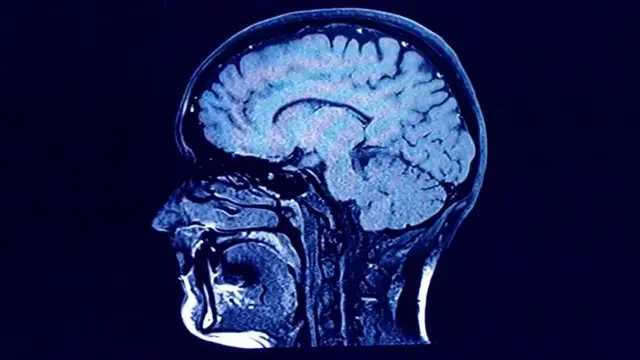

Spaulding na wenzake walifanya tafiti mwaka wa 2013 kwa kutumia mbinu za kutabiri umri wa kitu kwenye seli za ubongo wa binadamu zinazoitwa nyuroni. Kwa miaka mingi, watafiti wamefikiri kwamba idadi ya niuroni katika ubongo wa mwanadamu huwekwa utotoni.

Katika gamba la ubongo, matokeo ya tafiti za awali za kikundi cha Spalding yaliakisi uelewa wa watafiti kuhusu niuroni.

Lakini kwa kutumia Carbon dating katika eneo la hippocampus ya ubongo, timu ya Spalding iligundua kuwa niuroni mpya zinaweza kuzalishwa katika maisha yote ya mtu, hata baada ya kufikia uzee.

Matokeo ya utafiti, yaliyochukuliwa kuwa hatua kubwa katika tiba ya nyuroni , yamesababisha mikakati ya kimatibabu ya kuzuia upotezaji wa nyuroni unaosababishwa na ugonjwa na kuongeza idadi ya niuroni mpya.